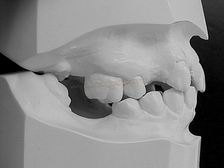

MODELOS DE ESTUDO EM GESSO (vista latera direita) |

MODELOS DE ESTUDO EM GESSO (vista latera esquerda) |

MODELOS DE ESTUDO EM GESSO (vista frontal) |